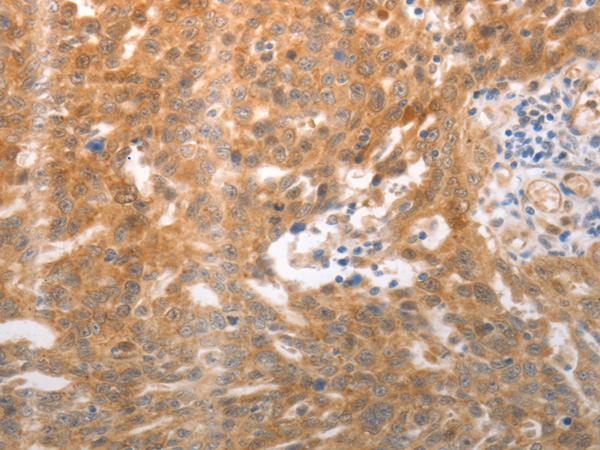

分类: 科研抗体货号: P11263别名: P2Y11应用: WB,IHC反应种属: Human